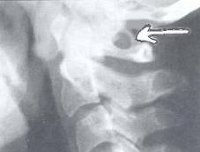

При обращении пациента с симптомами недостаточности кровообращения в вертебро-базилярном бассейне головного мозга в первую очередь производят рентгенографию черепа и рентгенографию позвоночника в шейном отделе. Аномалия Кимерли, как правило, достаточно четко визуализируется на боковых рентгенограммах области краниовертебрального перехода. При наличие ушного шума для исключения лор-патологии (кохлеарный неврит, хронический средний отит, лабиринтит) может потребоваться консультация отоларинголога, проведение аудиометрии и других исследований слуха. Производится также исследование вестибулярного анализатора (вестибулометрии, электронистагмографии, стабилографии).